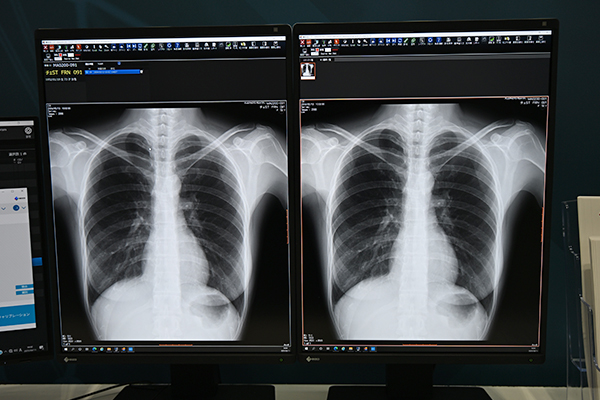

このほか,画像診断用モニターとして,USB Type-C入力端子を搭載した「RadiForce RX670」も関心を集めた。PCや周辺機器との接続が容易になり,快適な読影環境を構築できる。外装などには再生プラスチック採用し,梱包の簡素化を図るなど環境に配慮した製品であることも忘れてならない特長である。

USB Type-C入力端子を搭載した「RadiForce RX670」